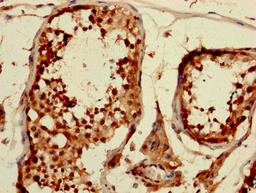

IHC image of CSB-PA005086DA01HU diluted at 1:1200 and staining in paraffin-embedded human testis tissue performed on a Leica BondTM system. After dewaxing and hydration, antigen retrieval was mediated by high pressure in a citrate buffer (pH 6.0). Section was blocked with 10% normal goat serum 30min at RT. Then primary antibody (1% BSA) was incubated at 4°C overnight. The primary is detected by a biotinylated secondary antibody and visualized using an HRP conjugated SP system.